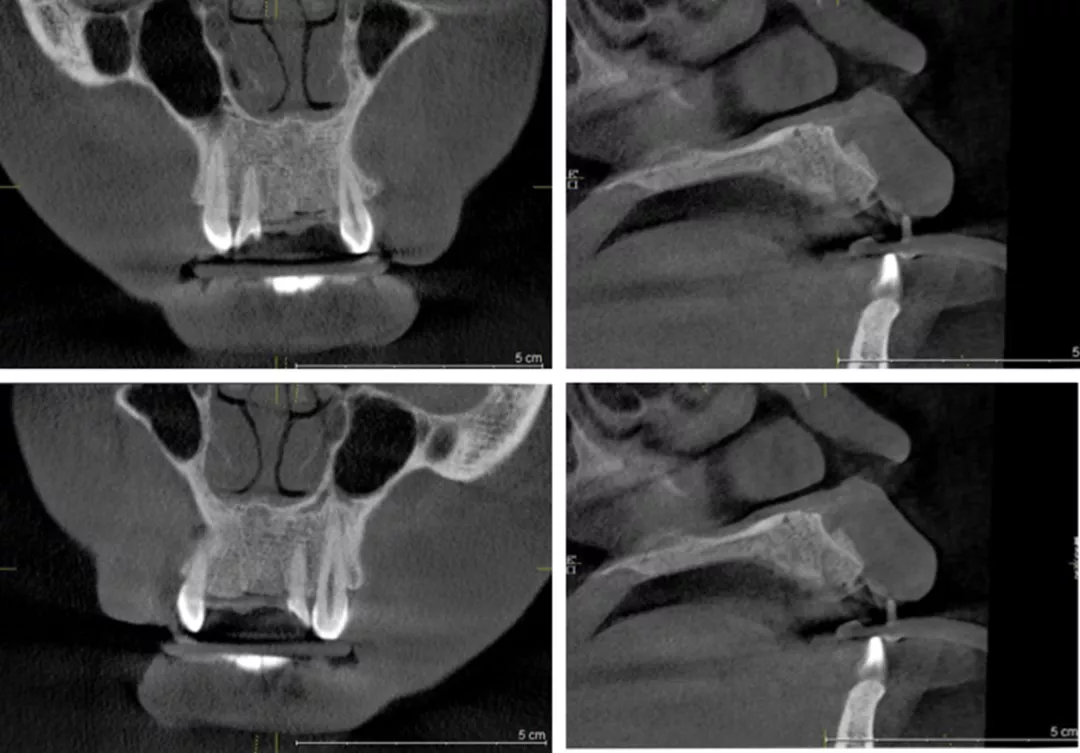

影像学检查

·      #11根中至根尖1/3折裂,桩核无断裂影像。根长7-8mm。根方牙槽骨偏腭侧埋伏近远中向多生牙。

·      #21腭侧根中/3折裂,牙周膜增宽,桩核无断裂影像。根长7-8mm,冠根比不足。

术后影像学检查